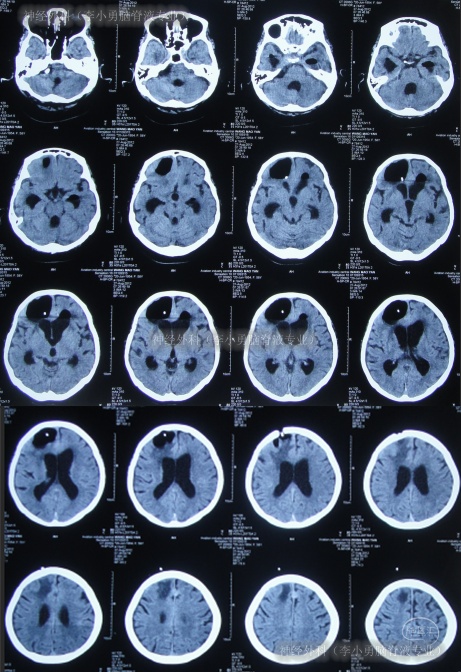

但2012年6月13日(第5家医院治疗22天)凌晨3点患者突发昏迷,体温39.6℃,测血压130/90mmHg,查头颅CT(图-10)后给予甘露醇、退热药物治疗后,体温可逐渐下降,但意识仍不见好转(家属叙述当时抢救了一天一宿)。

图-10:2012年6月13日头颅CT

2012年6月14日(第5家医院治疗23天),家属上午找到李小勇主任看过片子后确定可以接收,于是当天急诊转入李小勇脑脊液专业。